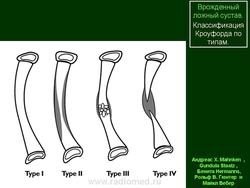

Классификация • По этиологии •• Врождённый •• Приобретённый • По виду •• Фиброзный ложный сустав без потери костного вещества •• Фиброзно-синовиальный ложный сустав (истинный ложный сустав) •• Ложный сустав с потерей костного вещества (дефект кости).